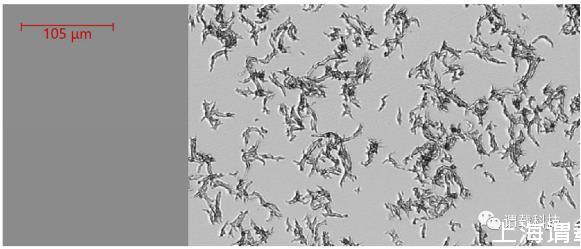

图3、Biosense微生物动态监测系统捕获的7h30分钟时刻对应的脓肿分枝杆菌(粗略表型)生长延时图(典型蛇形索成像)